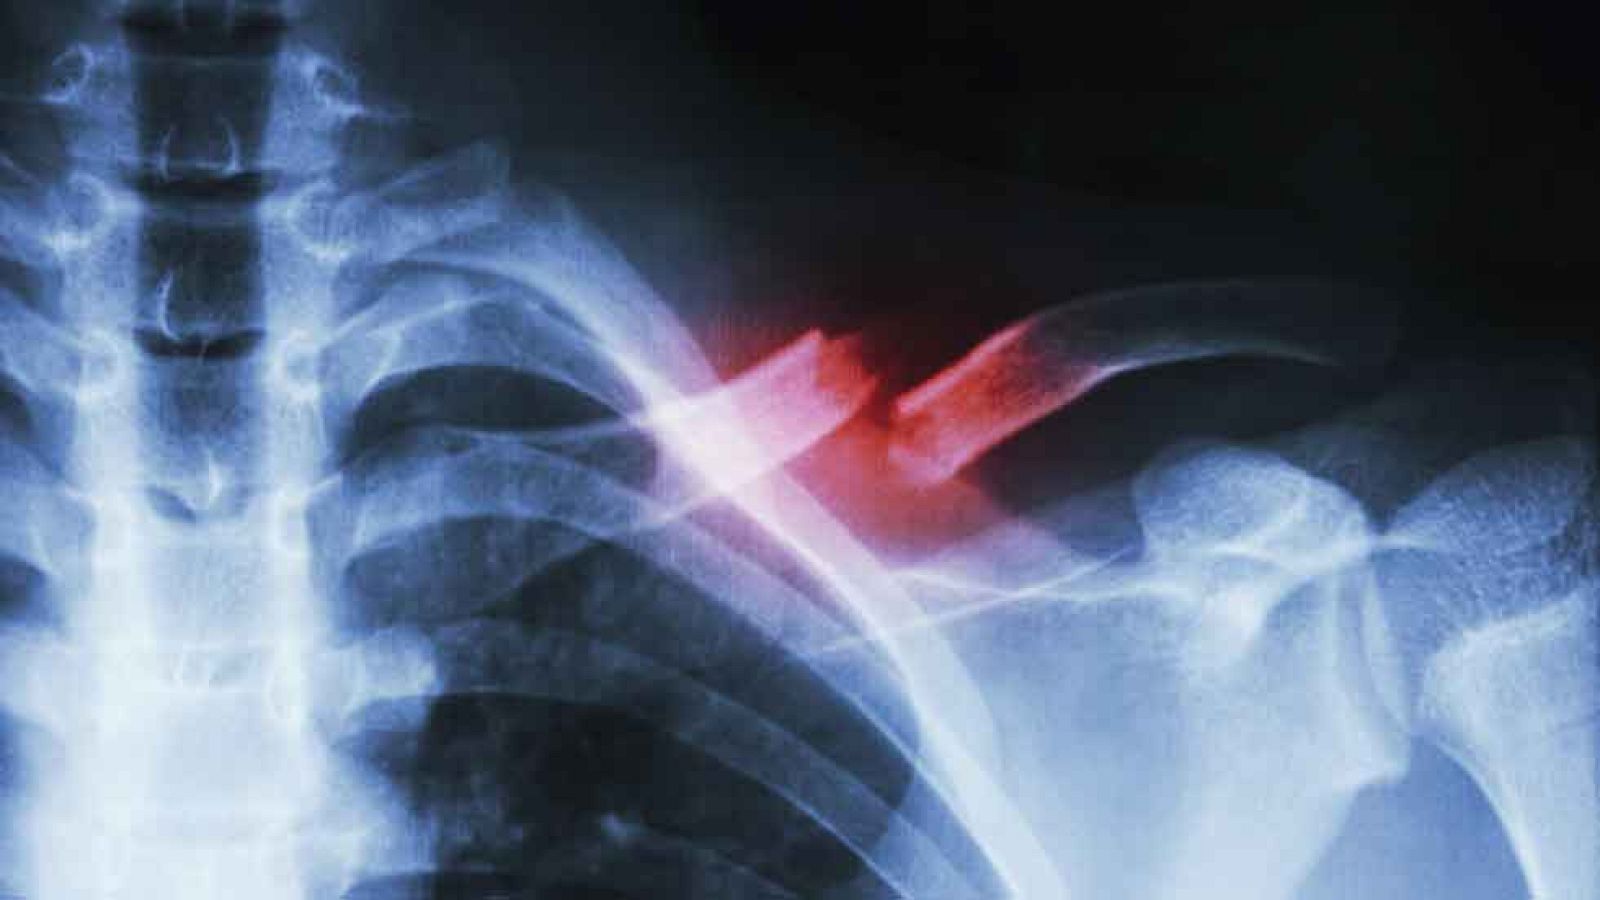

Para todos los públicos La falta de minerales: calcio y magnesio